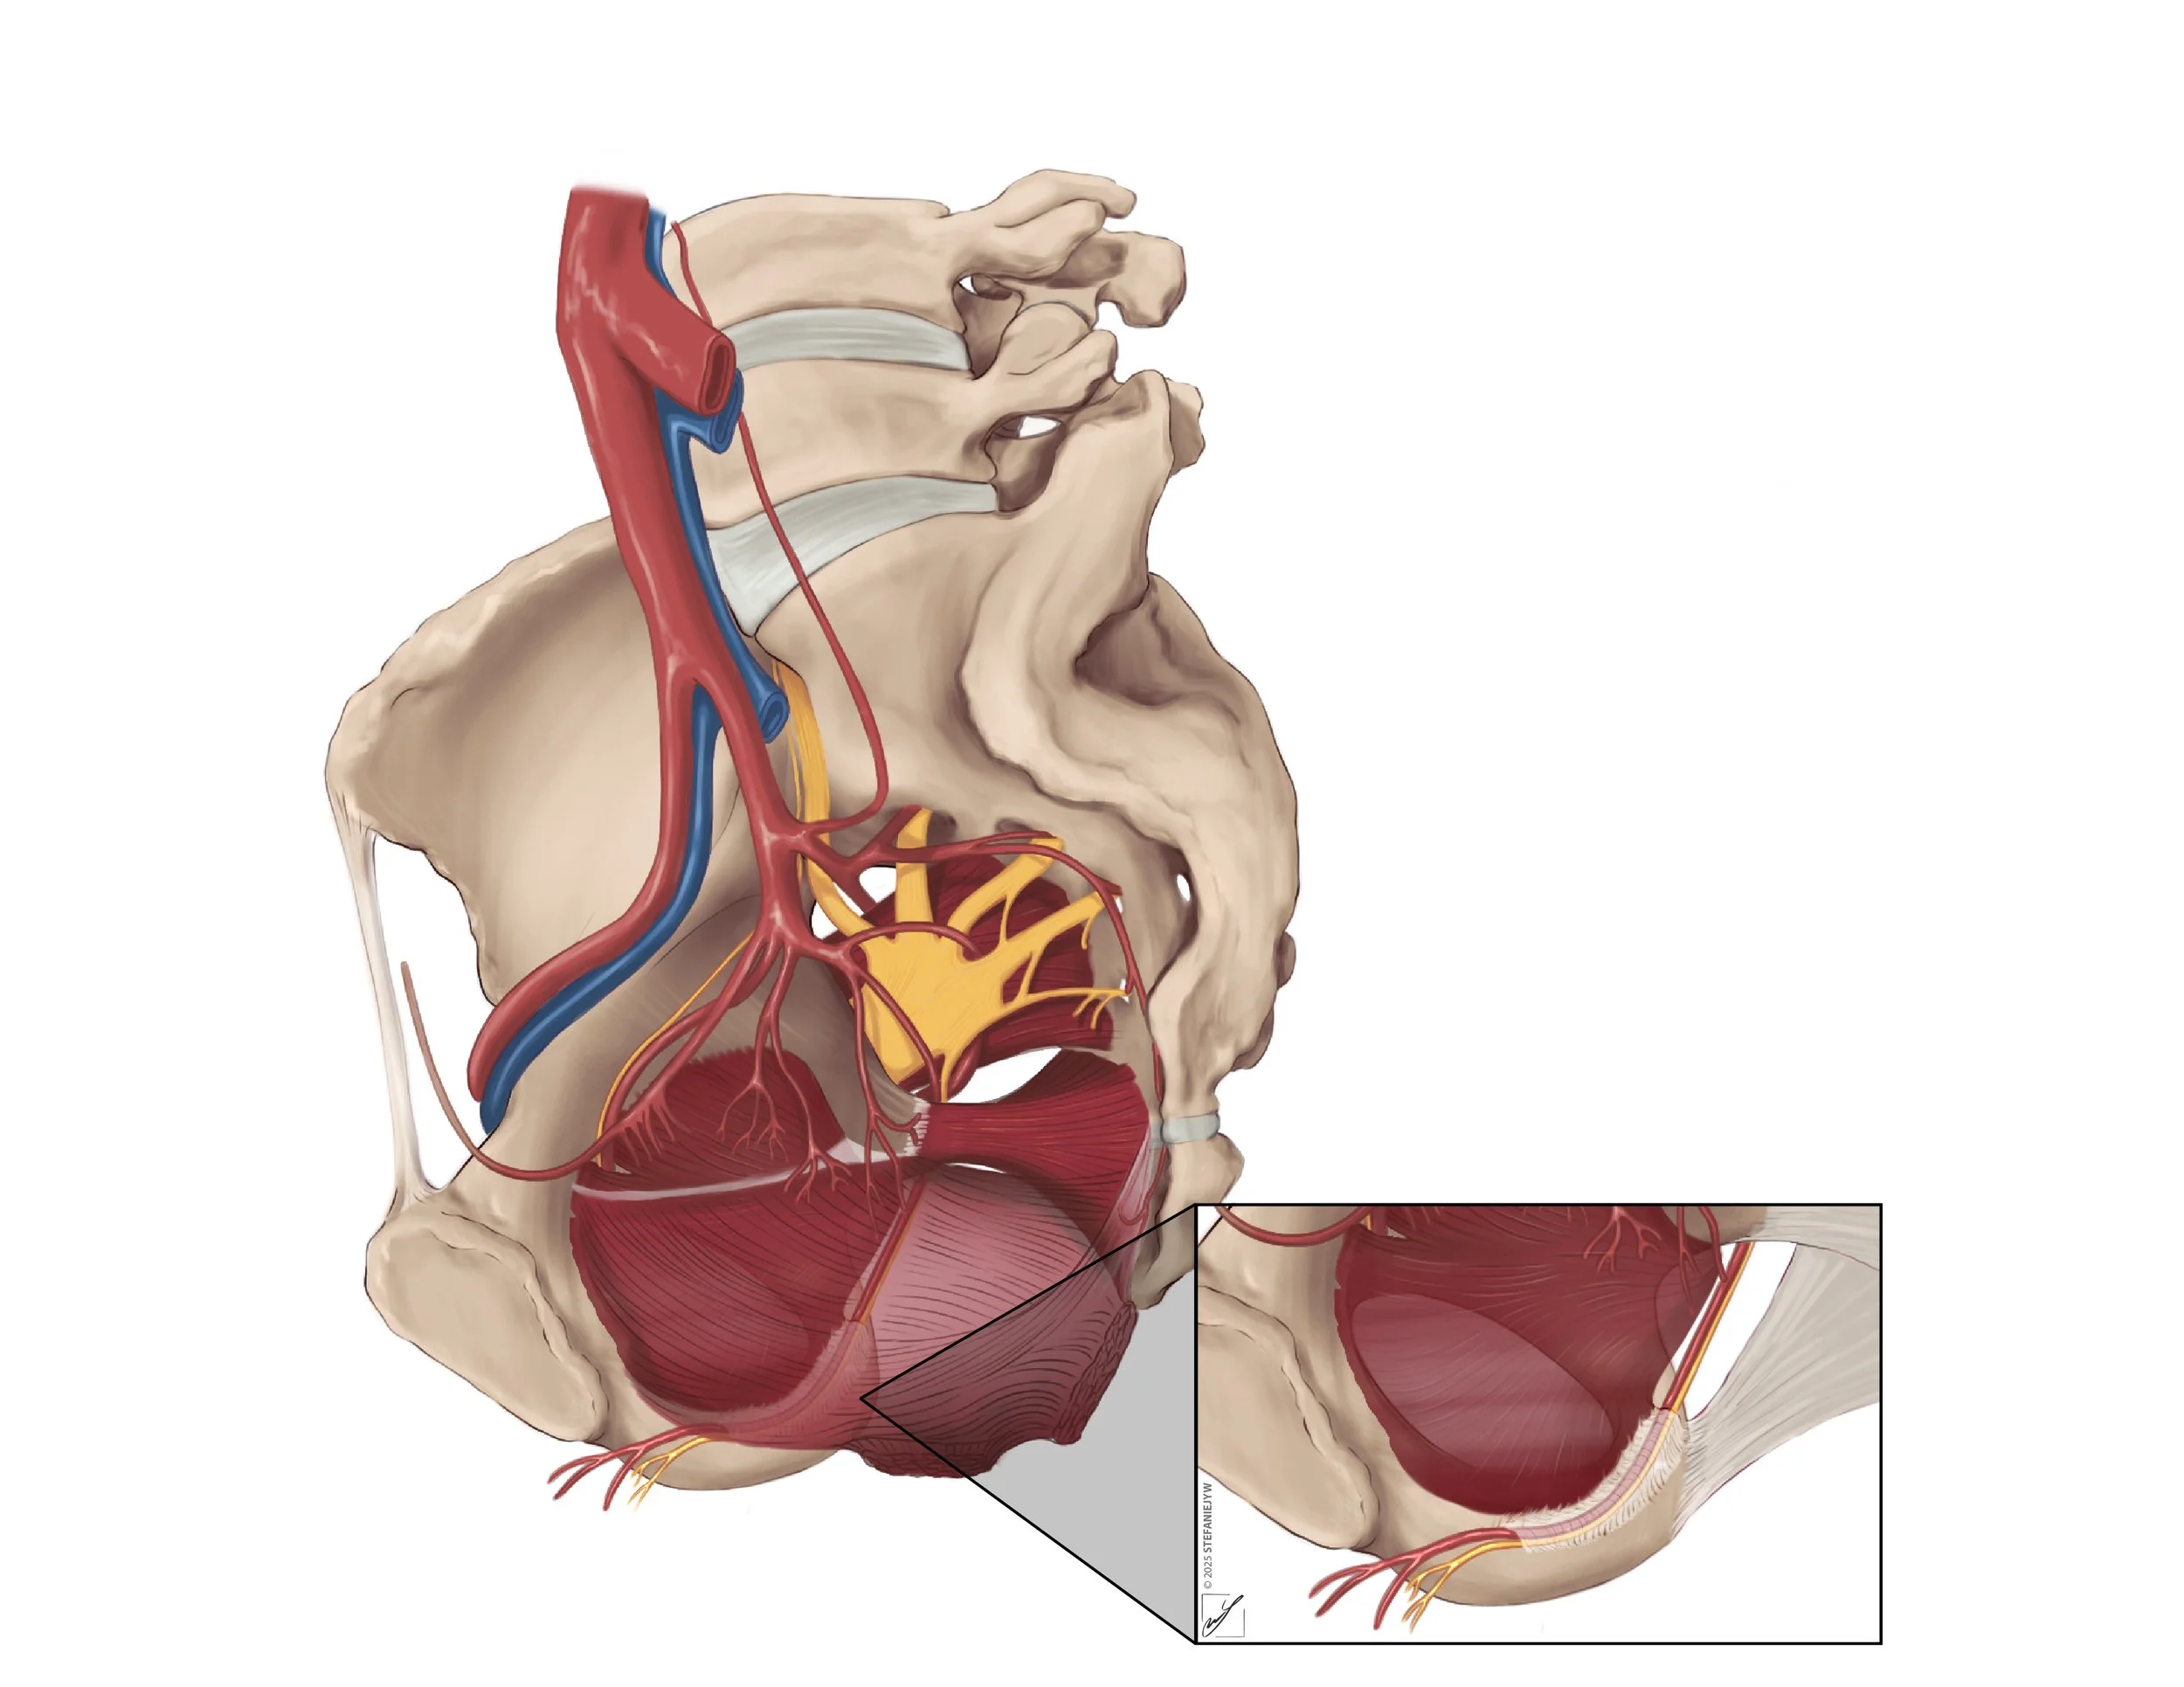

Series: Inclusive Anatomy